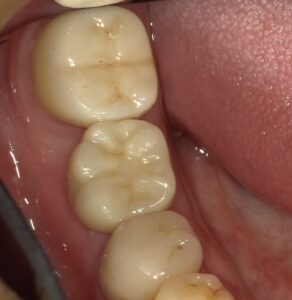

画像の様なイメージになります。針金を使いませんので

見た目がよくまた維持力も大きくとても良好な義歯となります。